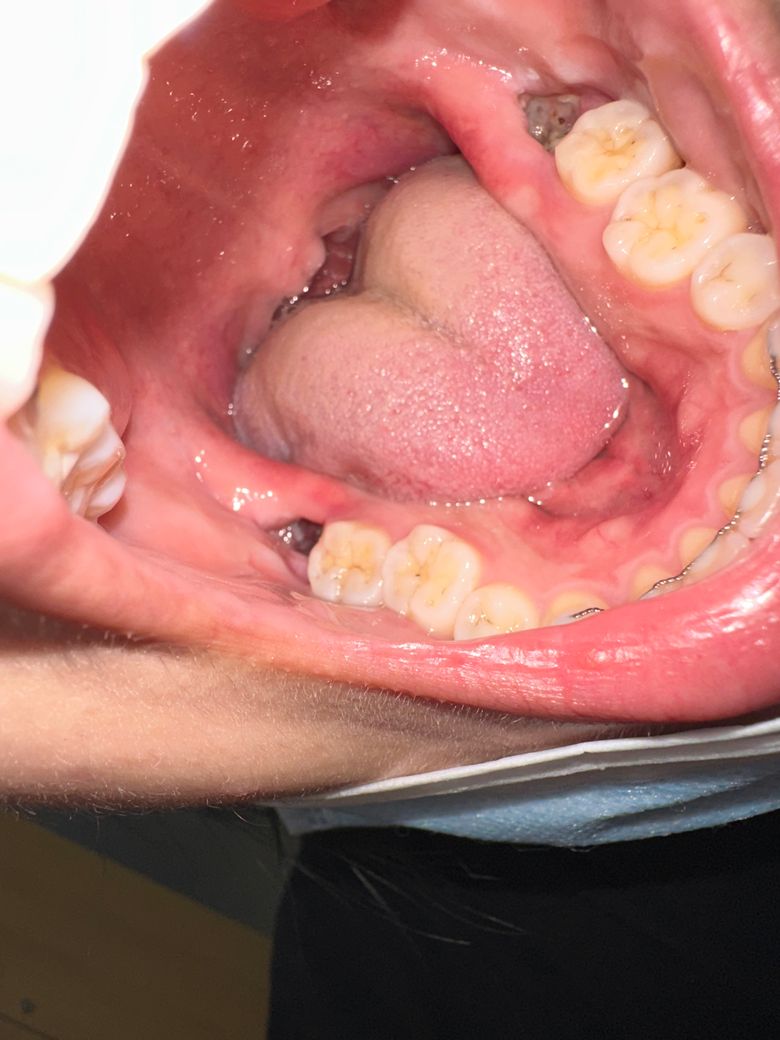

사랑니 발치 후 빈공간을 보면

사진처럼 흰색에 점있는 것들이 발치 후 남은 구멍에 있는데 음식물은 아닌 것 같아요 뭘까요? 통증도 있습니다

사랑니 발치후에는 상피세포가 하얗게 차오르면서 잇몸이 회복됩니다. 통증이 없으면 걱정안하셔도 됩니다.

사진상으로는 정확히 보이지는 않으나

아마 저 회색은 치유과정에 생긴 보호막인 상피조직일것입니다.